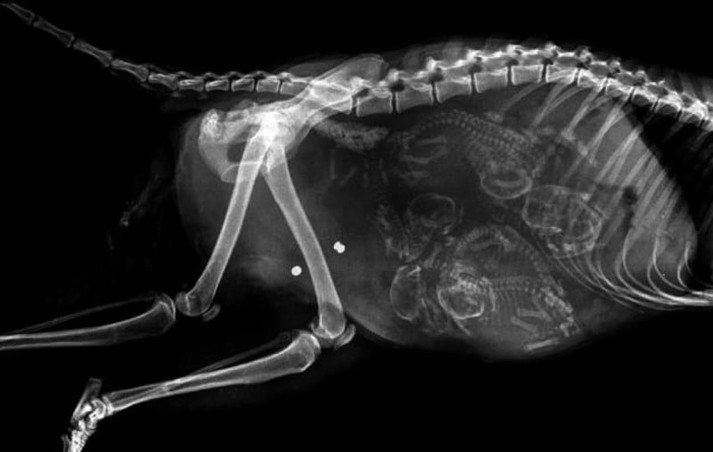

15 удивительных рентгеновских снимков беременных животных

Специалисты, которые по долгу своей работы наблюдают животных, готовых принести потомство, поделились этими удивительными рентгеновскими и ультразвуковыми снимками.